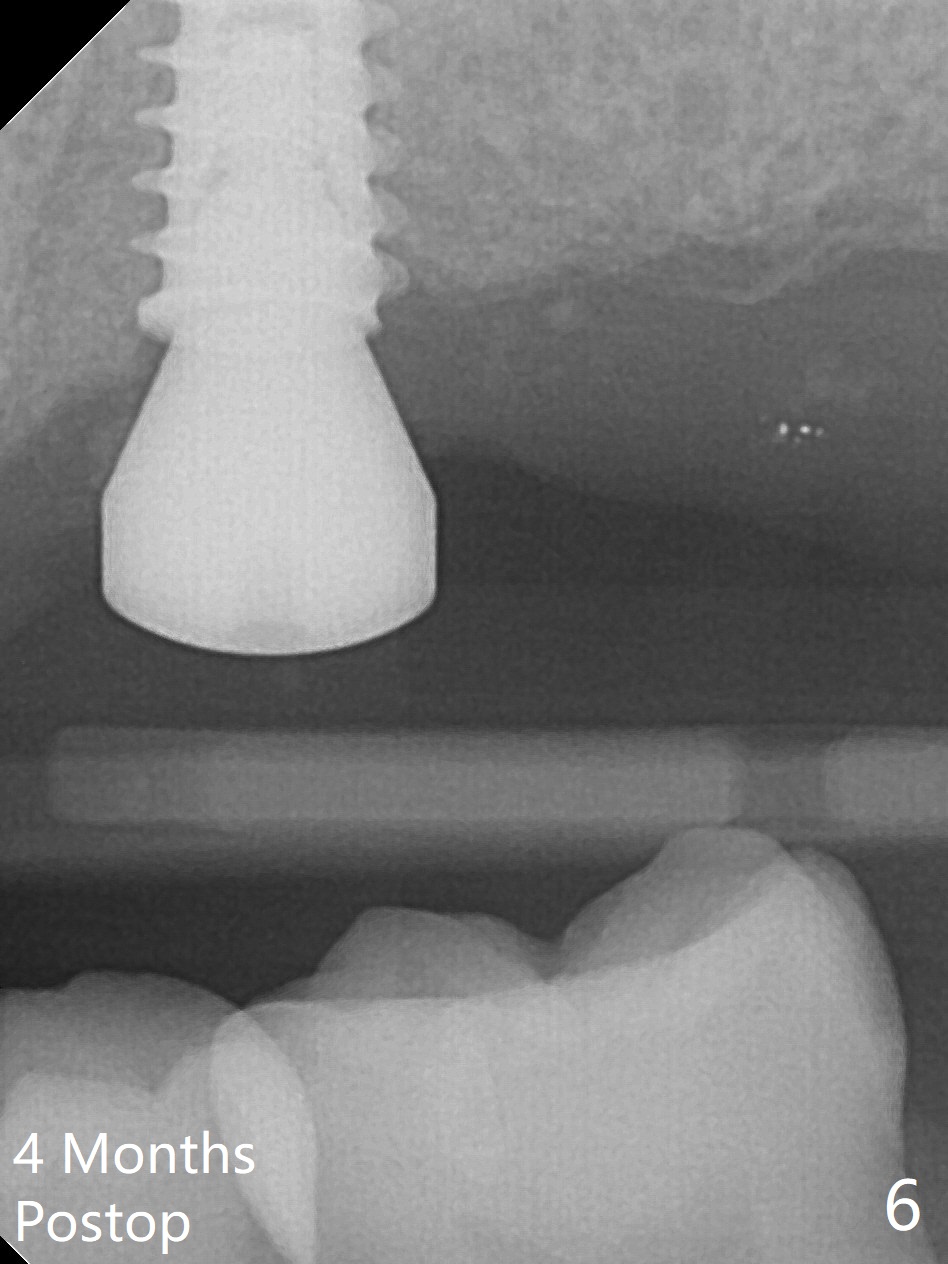

After extraction of the tooth #14 (Fig.1) and removal of granulation tissue associated with a distal fistula, a 1.6 mm drill is used to initiate osteotomy in the septum for 9 mm, followed by insertion of a 7 mm long parallel pin (Fig.2). The length of the subsequential osteotomy is 11 mm until 4.8 mm in diameter (overprep as will be shown below). The bone is hard so that sinus lift fails with 4.8 mm Magic Expander. Since a 5x9 mm dummy implant is placed with stability, a definitive implant with the same dimension is chosen with >50 Ncm (Fig.3,4). Prior to and after abutment placement, Vera graft is placed (*). The provisional perforates with loose abutment 3.5 months postop. A 6x4 mm healing abutment is placed. Osteointegration occurs 4 months postop (Fig.5,6).